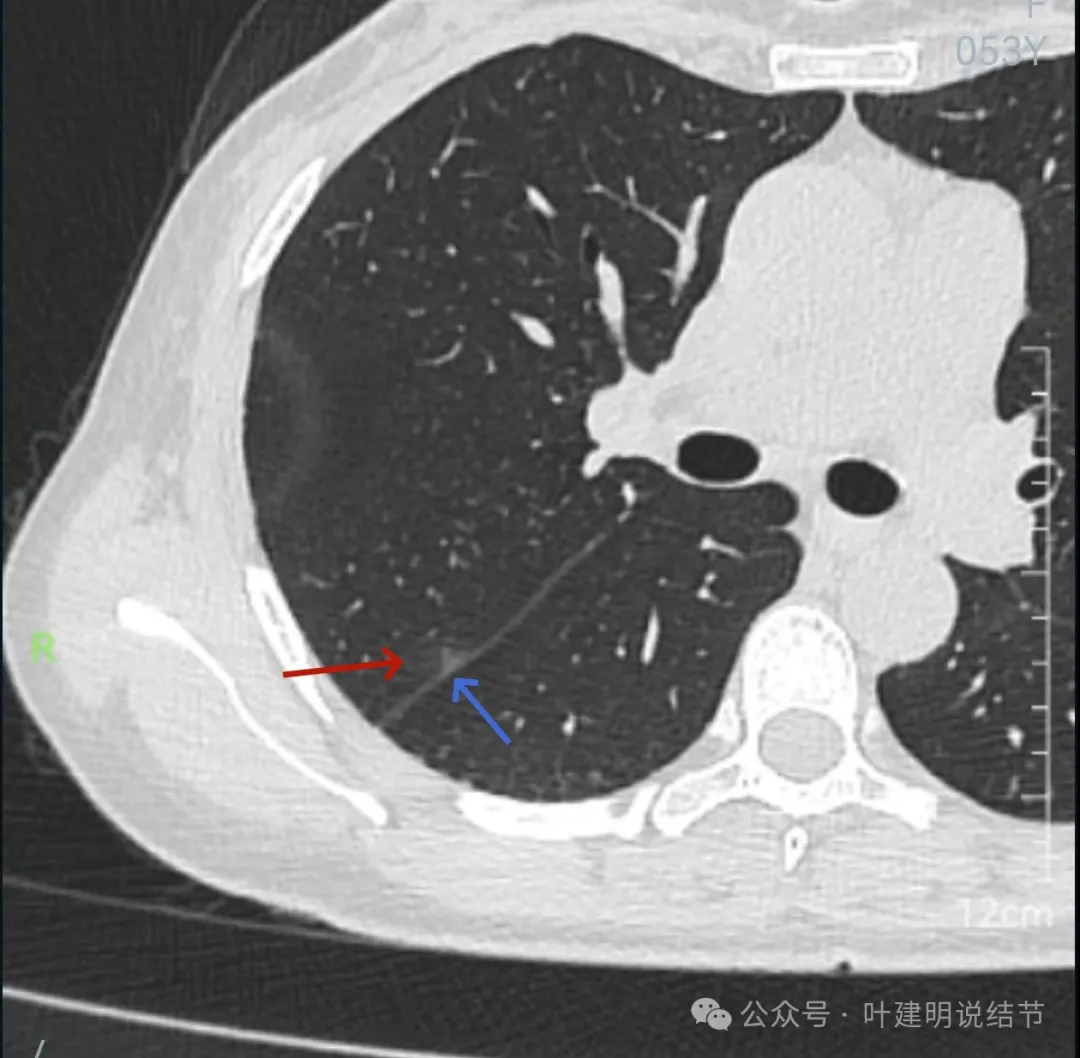

右上后段混合密度结节,瘤肺边界欠清,有明显实性成分,边缘不光滑。

右肺很淡的磨玻璃阴影,伴进入的血管异常增粗,整体轮廓尚显清楚。

右下叶背段边界欠清的磨玻璃影,有血管刚好位于病灶处。

蓝色的是实性的小结节,缺乏膨胀性,两次检查都有,没有变化,考虑是良性的;红色的这些事10月份检查新增的,这两处比较明显的9月份的时候就是绿色框起来这个区域,当时是没有的。短时间内出现、多发病灶、边缘模糊、轮廓欠清,没有恶性特征,与炎性病变符合。建议查查隐球菌方面的化验,如此结果阳性,请呼吸内科或感染科处理。意见供参考!

病灶出现,轮廓不清,瘤肺边界模糊,有血管穿行,血管有异常增粗。

血管壁有异常密度增高,病灶混合密度,轮廓总体在此层较清,但瘤肺边界不清。

病灶偏实性部分不密实,磨玻璃部分过淡且模糊。

边缘有毛刺,但不够锐利;外周磨玻璃成分密度过淡且界限不清;实性部分也显得不致密;与叶间裂距离近但没有任何牵拉影响。

实性成分在灶内看,也是界限不清,磨玻璃部分淡而糊。

整体感觉像病灶中间偏实性些的成分伴外周晕征。

边缘区域离叶间裂更近,仍无牵拉。

几乎贴着叶间裂了,仍无任何牵拉影响。

病灶密度边缘部分也不均,离叶间裂近而没有影响。

上图病灶已经贴着叶间裂,但仍显示是平直的,没有任何牵拉影响。